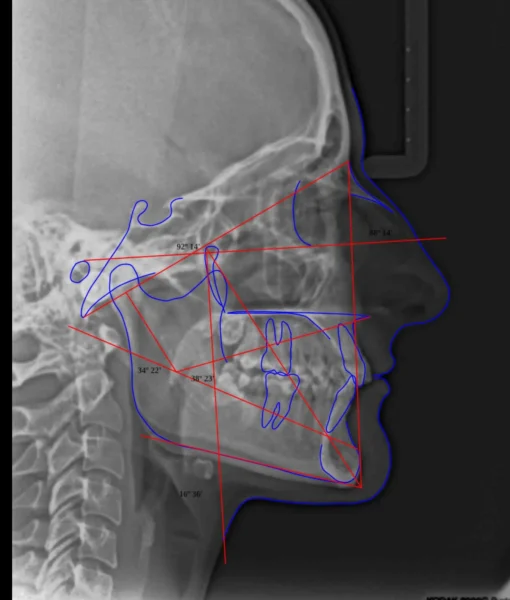

En Ident3D, nos enorgullece ofrecer un conjunto completo de cefalogramas de última generación, respaldados por tecnología avanzada y un enfoque centrado en la precisión y la excelencia en la ortodoncia. Nuestros cefalogramas proporcionan una visión detallada de la anatomía facial y craniofacial, permitiendo una planificación precisa y personalizada de los tratamientos.

- Bjork-Jarabak: Utilizamos la técnica Bjork-Jarabak para evaluar las proporciones y relaciones dentomaxilares y esqueléticas, proporcionando una base sólida para la planificación ortodóncica.

- Harvold: El cefalograma Harvold es fundamental para analizar el crecimiento facial y las relaciones dentales. Proporciona información valiosa para el diseño de tratamientos ortodóncicos y ortopédicos.

- McNamara: Con el cefalograma McNamara, evaluamos la posición de los maxilares y mandíbula, permitiendo una planificación detallada para tratamientos ortodóncicos y ortopédicos.

- Ricketts Completo: Ofrecemos el cefalograma Ricketts completo para una evaluación global de las estructuras faciales y maxilofaciales, contribuyendo a un enfoque integral en la planificación de tratamientos.

- Ricketts Frontal: El cefalograma Ricketts frontal proporciona una vista específica de las relaciones esqueléticas frontales, permitiendo una planificación precisa para correcciones ortodóncicas.

- Schwartz: Utilizamos el cefalograma Schwartz para evaluar la posición de los maxilares y la mandíbula, brindando información crucial para tratamientos ortodóncicos y ortopédicos.

- Steiner: El cefalograma Steiner se enfoca en las relaciones dentomaxilares y proporciona medidas específicas para la planificación de tratamientos ortodóncicos.

- VERT (Vertical Esthetic Subspinale): Evaluamos la estética facial vertical con el cefalograma VERT, una herramienta valiosa para planificar tratamientos ortodóncicos y ortopédicos.

- Gianni Pistoni: Utilizamos el cefalograma Gianni Pistoni para evaluar la posición y relaciones de los maxilares, aportando datos precisos para la planificación ortodóncica.